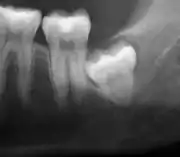

وجدت إحدى المراجعات أن 11٪ من ضروس العقل سيكون لها دليل على المرض ويجد لها [أعراض]، و 0.6٪ سيكون لديهم الأعراض لكن ليس لديهم مرض، و 51٪ سيكونون بدون أعراض لكن لديهم مرض حاضر، و 37٪ سيكونون بدون أعراض وليس لديها مرض.[5] غالبًا ما يتم وصف ضروس العقل المنطمرة من خلال اتجاه انحرافها (المائلة للأمام أو بزاوية إنسية هي الأكثر شيوعًا) وعمق الانحراف وعمر المريض بالإضافة إلى عوامل أخرى مثل العدوى الموجودة مسبقًا أو وجود الأمراض (الخراجات ، الأورام أو التهاب عظم الفكين).[3]:143–144يتم استخدام كل من هذه العوامل للتنبؤ بصعوبة (ومعدل المضاعفات) عند خلع الضرس المنطمر.[6][7]

ضروس العقل المنطمرة التي لا يوجد لها اتصال بالفم، والتي ليس لها أي أمراض مرتبطة بالسن، ولم تسبب امتصاص الأسنان على الأسنان المجاورة، نادرًا ما تكون لها أعراض.[9] فرص حدوث مرض عند ضروس العقل المنطمرة التي لا يوجد لها اتصال مع الفم هي حوالي 12 ٪.[9] عندما تتصل ضروس العقل بالفم، فإن الطعام والبكتيريا تتغلغل حول الضرس وتتسبب في أعراض مثل الألم الموضعي، وتورم ونزيف الأنسجة التي تغمر السن. يُسمى النسيج الذي يحيط بالسن بغطاء السن ([./https://en.wikipedia.org/wiki/Operculum_(dentistry) operculum])، ويسمى هذا بـالتهاب ما حول التاج ([./https://en.wikipedia.org/wiki/Pericoronitis pericoronitis]) .[3]:141 يحدث التهاب اللثة المزمن ذو الدرجة المنخفضة عادة في ضرس العقل أو الضرس الثاني، مما يسبب أعراضًا أقل وضوحًا مثل رائحة الفم الكريهة ونزيف اللثة. يمكن أن تظل الأسنان أيضًا بدون أعراض (خالية من الألم) ، حتى مع وجود مرض.[5]